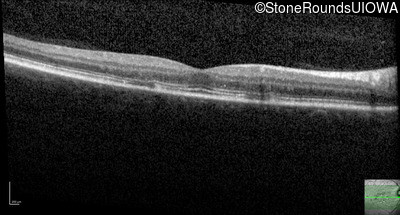

Optical Coherence Tomography - Right - 20/15

Exemplar / OCT Stack

OCT Stack